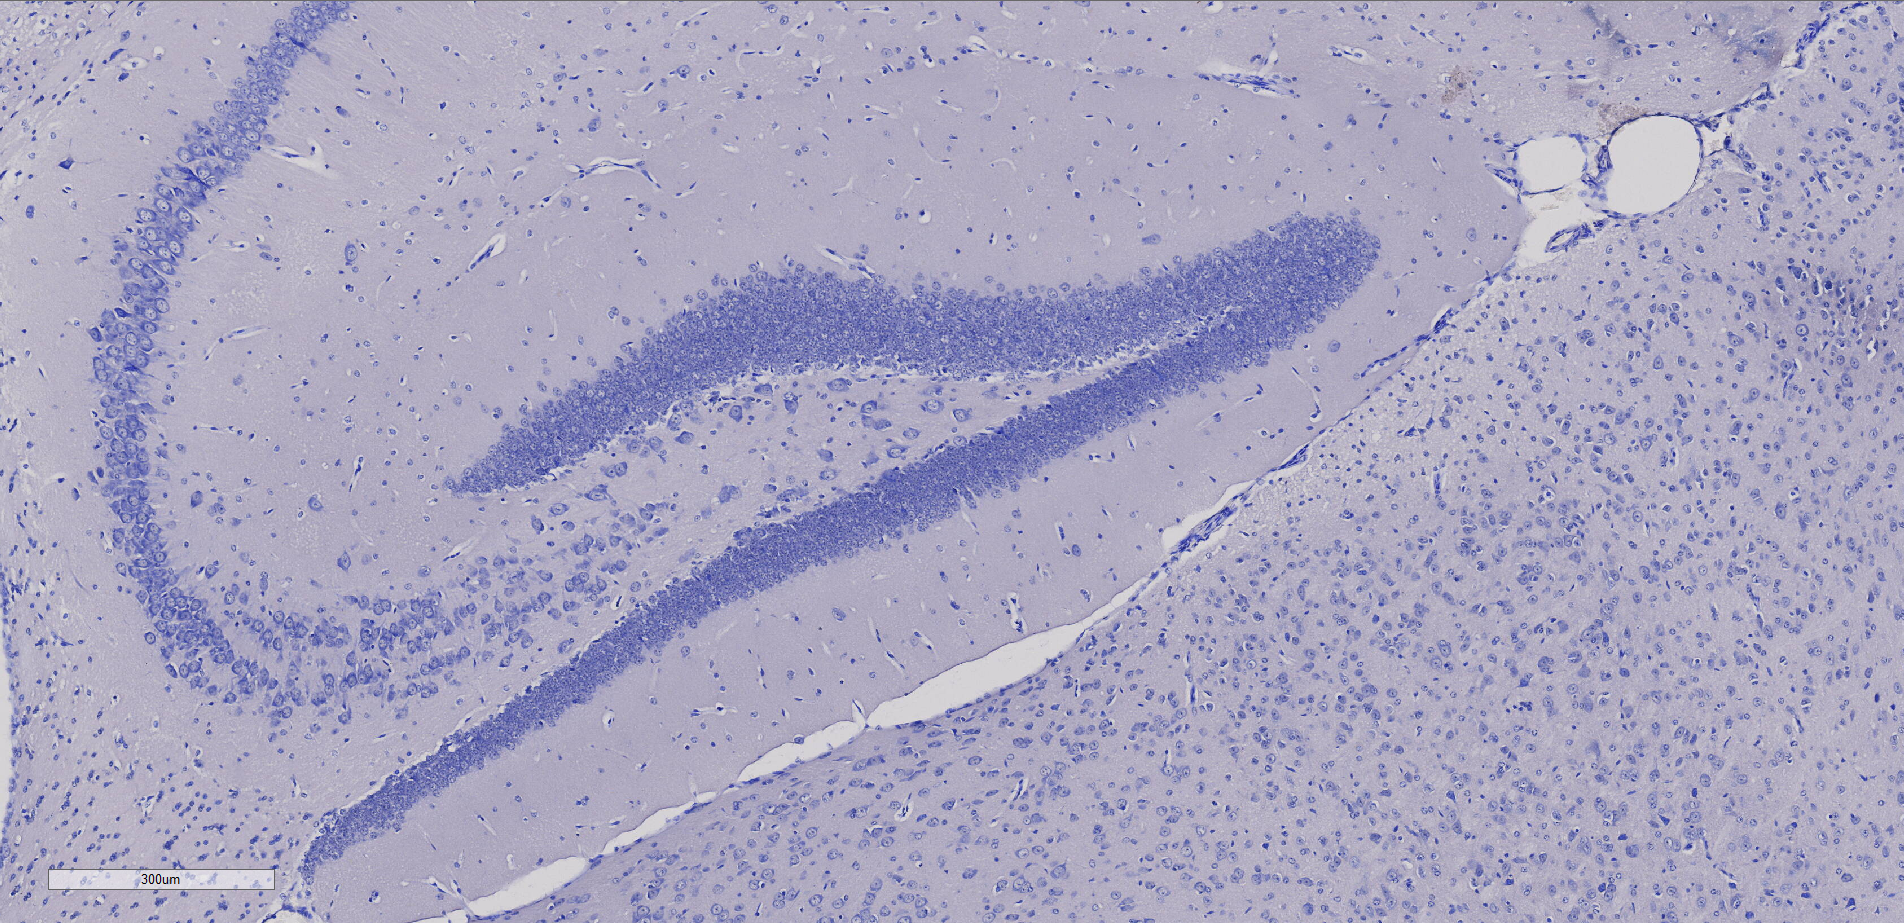

尼氏染色

尼氏染色法利用碱性染料对神经组织进行染色,以强调细胞质中的尼氏体。尼氏体是一种嗜碱性物质,分布广泛于各类神经元中,其形状、大小和数量在不同神经元中呈现差异。通过运用尼氏染色法,能够有效染显尼氏体,从而观察神经元内的细胞结构,并通过对尼氏体的观察来评估神经元是否受损。焦油紫、亚甲蓝、甲苯胺蓝和硫堇等是常用的碱性染料。这一技术为深入研究神经组织提供了强大的工具,使科学家得以更全面地了解神经元的结构和状态。

小鼠脑部整体尼氏染色 海马结构 尼氏小体